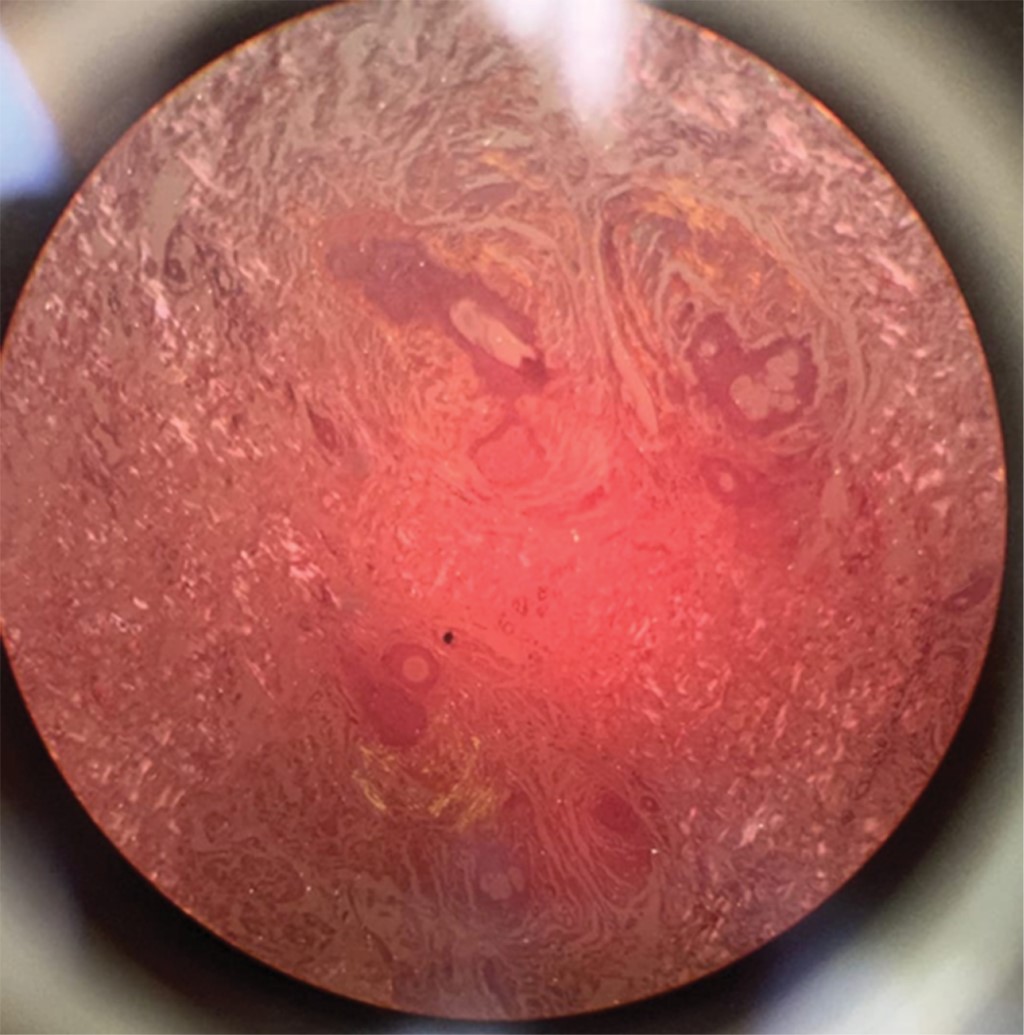

Se le realizó biopsia de la lesión localizada en hueco axilar, en la cual se observó queratosis seborreica reticulada y depósito perianexial focal de material amiloide. Tinción rojo Congo positivo (Figura 3), con lo que se consolida el diagnóstico de amiloidosis cutánea.

La tinción con rojo Congo, que exhibe una birrefringencia característica bajo luz polarizada cruzada, sigue siendo el estándar de oro.6

Figura 3